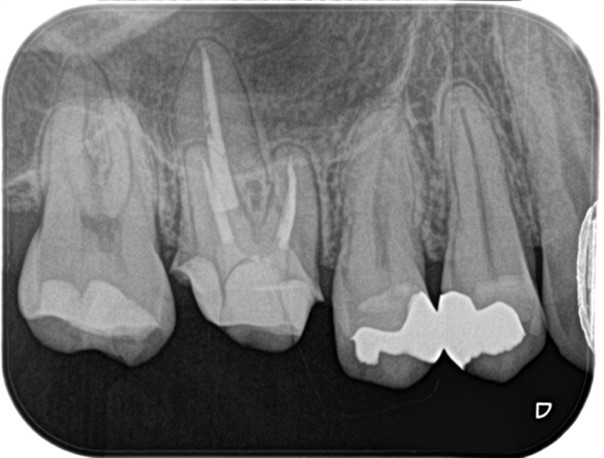

_治療後のレントゲン画像|目白マリア歯科.jpg)

2回目の治療にて根管充填、支台築造処置まで終了しました。

2回目の治療開始時(1回目の治療から1週間経過後)には痛みは完全に消失していました。今後仮歯を製作し、問題がなければ最終補綴処置(被せもの)の製作に移行します。